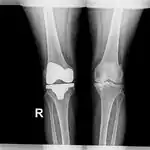

| Cancerous (Chondrosarcoma) | Conventional chondrosarcoma grade I (axial skeleton)-III[1][2] |

|